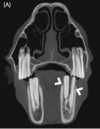

What is the lesion identified on the CT ? Is this relevant in the context of HSK ?

Transverse image of the head at the level of 09s maxillary cheek teeth. There is **gas within the infundibulum** of both 109 and 209 (arrows). This is considered an **incidental finding**. ## Footnote Computed tomography findings in horses presented with signs of head-shaking evj 23